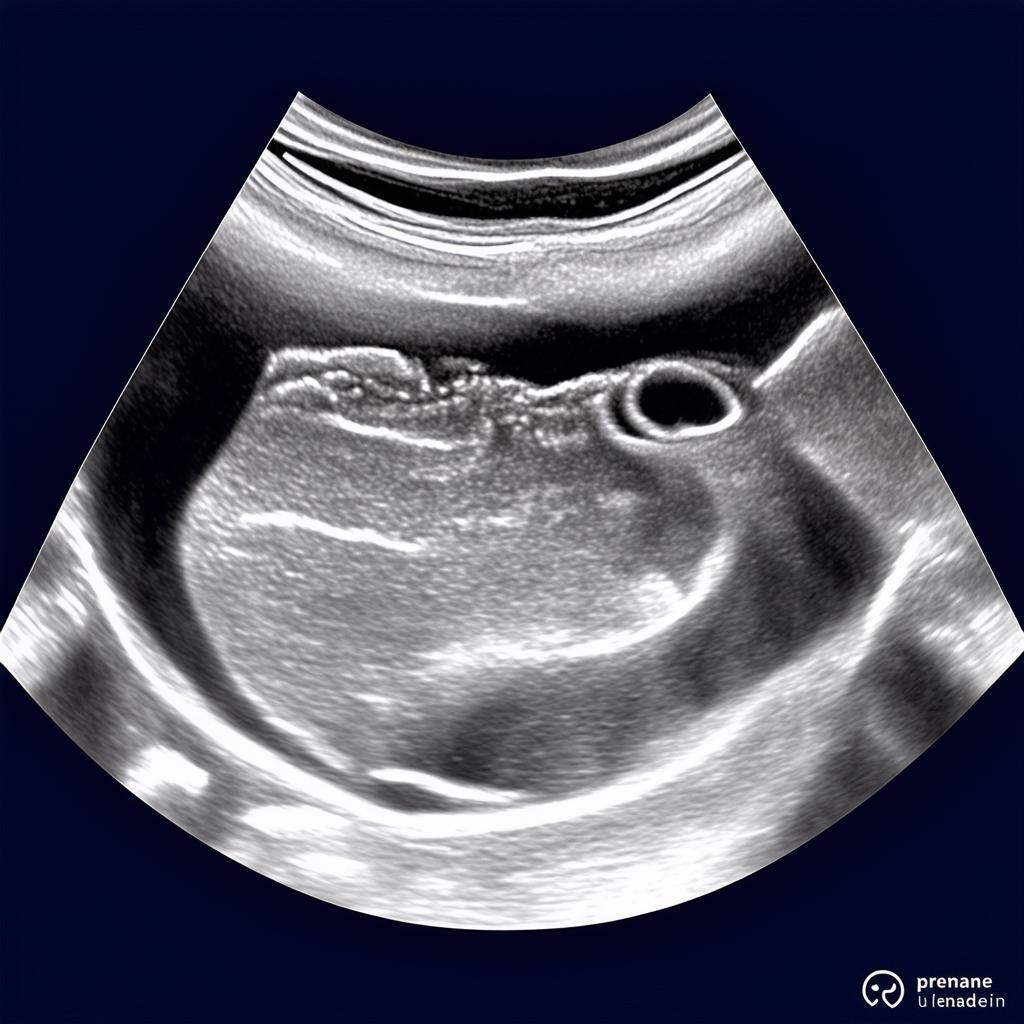

33 неделя беременности — это важный этап в развитии плода. В этот период ребенок активно растет и набирает вес, готовясь к появлению на свет. По данным УЗИ, норма веса плода на 33 неделе составляет примерно 1900–2200 граммов, а его рост достигает 42–44 см. Однако эти показатели могут варьироваться в зависимости от индивидуальных особенностей.

Контроль веса ребенка на 33 неделе беременности позволяет врачам своевременно выявить возможные отклонения в развитии. Слишком низкий вес может указывать на задержку роста, а избыточный — на риск осложнений во время родов. Регулярные УЗИ и консультации с врачом помогают обеспечить здоровое течение беременности.

Если УЗИ показывает значительные отклонения в весе ребенка, врач может назначить дополнительные исследования, такие как допплерометрия или КТГ. В некоторых случаях рекомендуется коррекция питания или медикаментозная терапия. Главное — не паниковать и строго следовать рекомендациям специалиста.